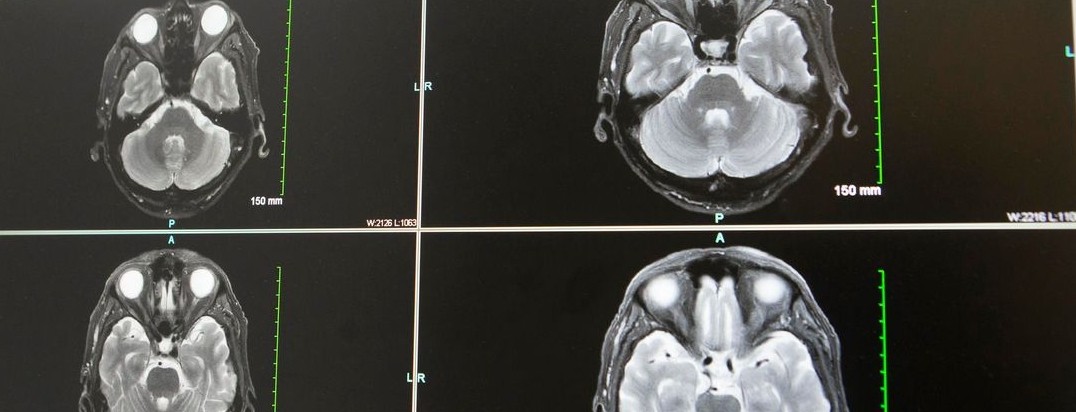

Featured photo at top of brain scans. Photo courtesy of Joseph Broderick.